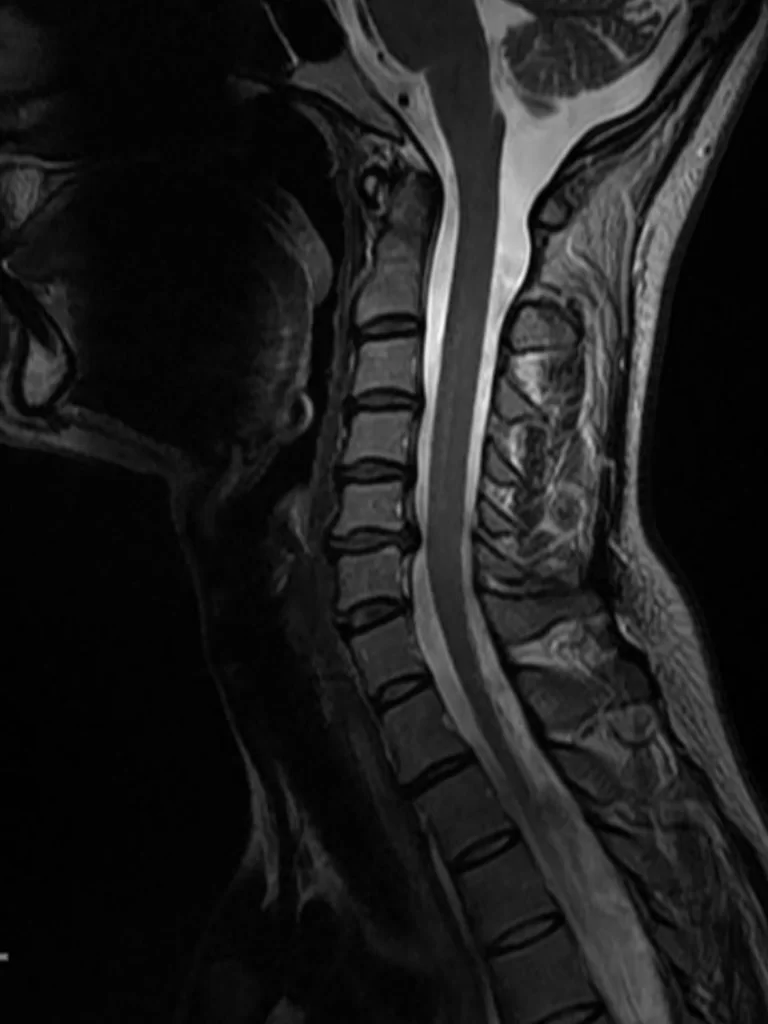

Σωματεκτομή Α6 Σπονδύλου

Ασθενής γυναίκα 57 ετών με αιμωδίες αριστερού άνω άκρου, αυχεναλγία και διαταραχή βάδισης. Ο απεικονιστικός έλεγχος έλεγχος με μαγνητική και αξονική τομογραφία της αυχενικής μοίρας